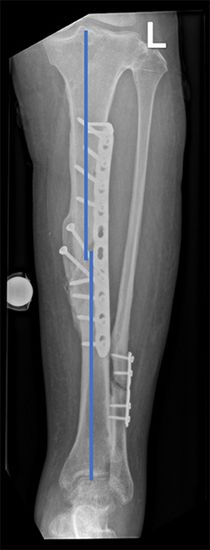

Eine Fehlstellung kann nur durch eine Operation korrigiert werden. Die Planung der Korrektur erfolgt klassischerweise anhand zweier Röntgenbilder – von vorne und von der Seite. Um den Knochen wieder in seine möglichst ideale Form zu bringen, werden häufig sogenannte Knochenblocks (aneinanderhängendes Knochenstück) eingebracht oder entfernt. Ist die Fehlstellung aber in beiden Ebenen (von vorne und von der Seite) oder zusammen mit einer Rotationsfehlstellung, ist eine ganzheitliche, dreidimensionale Korrektur mit diesem Verfahren nur eingeschränkt möglich.

Unser eigens dazu entwickeltes Computermodell berücksichtigt jedoch die Dreidimensionalität der Deformität. Unsere Software ermöglicht zudem die genaue Planung der Korrektur anhand des anderen Beins *, *. Häufig kann damit die Fehlstellung korrigiert werden, während weniger oder gar kein Knochen eingebracht oder entfernt werden muss. Der Grund dafür ist die genau berechnete Ebene, in welcher der Knochen durchtrennt und gedreht wird.

Für eine äusserst genaue operative Umsetzung der Korrektur wird diese nicht freihändig durchgeführt, sondern anhand von Schablonen, die exakt auf den Knochen der Patientin oder des Patienten angefertigt wurden (patientenspezifische Schablonen). Um den Knochen in die richtige Position zu bringen und zu halten, werden weitere Schablonen eingesetzt. Diese halten den Knochen zudem genau in der gewünschten Position, bis er mittels Schrauben und Platten fixiert wird.